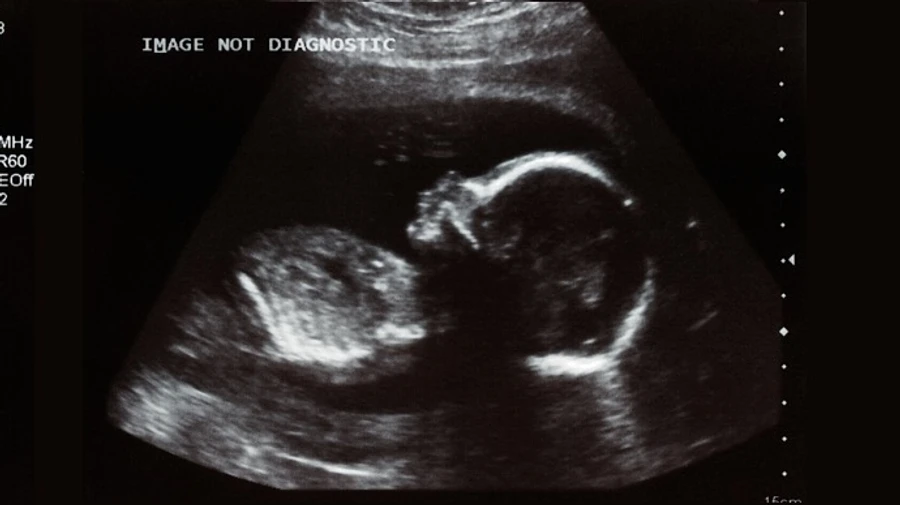

Деталі: Вивчивши історію хвороби дитини та породіллі з COVID-19 дослідники прийшли до висновку, що коронавірус може передаватися від вагітної жінки до плоду.

У дослідженні йдеться про дитину, яка народилася в березні 2020 роки від матері з діагнозом COVID-19 і незабаром дала позитивний результат на згадану хворобу. Тоді у немовляти діагностували аномалії в мозку, проте дитина перемогла хворобу і через 3 місяці "має медичні показання близькі до норми". 23-річна мама дитини, історія хвороби якого тепер вважається першим випадком внутрішньоутробного зараження коронавірусом, також одужала від COVID-19